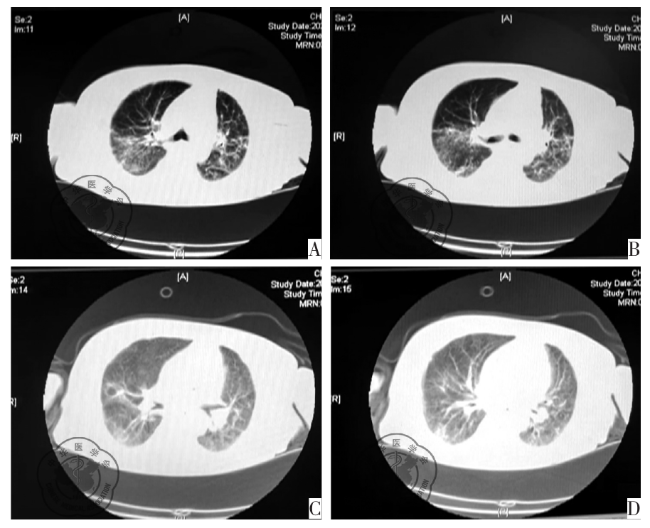

图1 患者胸部CT扫描双肺纹理增多、增粗,双肺野透光度大,双肺野外周带胸膜下可见囊状透光影,双肺可见散在片架状密度增高影,双肺内多发斑片、条索状密度增高影,双上肺可见小钙化灶

患者经40 d综积极救治后,生命体征平稳:体温正常,氧合指数>300 mmHg,炎性指标恢复正常,于2024年5月29日转呼吸科继续治疗。出院前复查:胸部CT示双肺炎症吸收80%;肾功能恢复,血小板及凝血功能正常。随访2个月显示患者意识清楚,可配合床旁康复训练,改良Rankin量表评分4分。